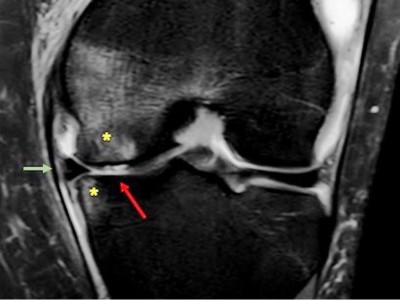

Knieschmerzen diagnostizieren per Ultraschall

Ist das Kniegelenk entzündet? Liegt ein Muskelriss vor? Sind Bänder, Knorpel oder Knochen verletzt? Die Ultraschalluntersuchung kann bei Schmerzen im Knie schnell und zuverlässig die Ursache klären und therapieentscheidend sein.

Untersuchung des Beins eines Patienten/© Visionär / Fotolia, Sonographiequerschnitt über der Hälfte des M. quadriceps (Normalbefund)/© Gehlen M et al. / all rights reserved Springer Medizin Verlag GmbH, Eine Frau hält sich den Fuß am Knöchel/© dragana991 / Getty Images / iStock (Symbolbild mit Fotomodell), ZFA TALKS - Nackenschmerzen/© (M) contrastwerkstatt / Stock.adobe.com (Symbolbild mit Fotomodell), Fortgeschrittene Gonarthrose bei 83-Jähriger/© J. Stöve, Arzt untersucht Senior am Rücken/© miodrag ignjatovic / Getty Images / iStock (Symbolbild mit Fotomodellen), Frau mit Hut im Wald/© (M) encierro / stock.adobe.com (Symbolbild mit Fotomodell), Frau bei Knochenmineraldichte-Messung/© gelmold / stock.adobe.com (Symbolbild mit Fotomodell), Arzt untersucht Patienten mit Rückenschmerzen /© ChesiireCat / Getty Images / iStock (Symbolbild mit Fotomodellen), Frau geht Spazieren/© HODEI / stock.adobe.com (Symbolbild mit Fotomodell), Messung des Kopf-Wand-Abstands/© A. Schuh, Schmerzhafte Schwellung des linken Ellenbogens/© C. Raschka, Hallux rigidus Röntgenbefund/© A. Schuh, Coxarthrose rechts nach Kellgren-Lawrence-Grad III/© Dres. Lieser und Kollegen, Radiologische Praxis Trier, Sonografie am Fußgelenk/© A. Schuh, Gelenkultraschall am Knie/© A. Schuh, MRT bei medialseitiger Gonarthrose mit Knorpelschaden/© Klinikum rechts der Isar, Ultraschall am Ellenbogen/© A. Schuh, Position des Schallkopfs ventral an der Schulter/© So wie es am Bild steht, Röntgenaufnahmen von Valgus- und Varusachsen/© Schubert I et al. / all rights reserved Springer Medizin Verlag GmbH, Achillessehnenruptur/© Z. Binder, Ärztin behandelt Fußballspielerin mit Kopfverletzung/© rocketclips / stock.adobe.com (Symbolbild mit Fotomodell), Patientin mit Gonarthrose/© (M) FluxFactory / Getty Images / iStock (Symbolbild mit Fotomodellen), Search Icon, Die Leitlinien für Ärztinnen und Ärzte, Facharzttraining Allgemeinmedizin, Hand hält Laborröhrchen/© Kunstzeug / stock.adobe.com (Symbolbild mit Fotomodell), Läufer umfasst sein Sprunggelenk/© PeopleImages / Getty Images / iStock (Symbolbild mit Fotomodell), Herpes Zoster am Rücken/© Mumemories / Getty Images / iStock (Symbolbild mit Fotomodell), EKG befunden mit System - EKG Essential/© Springer Medizin Verlag GmbH